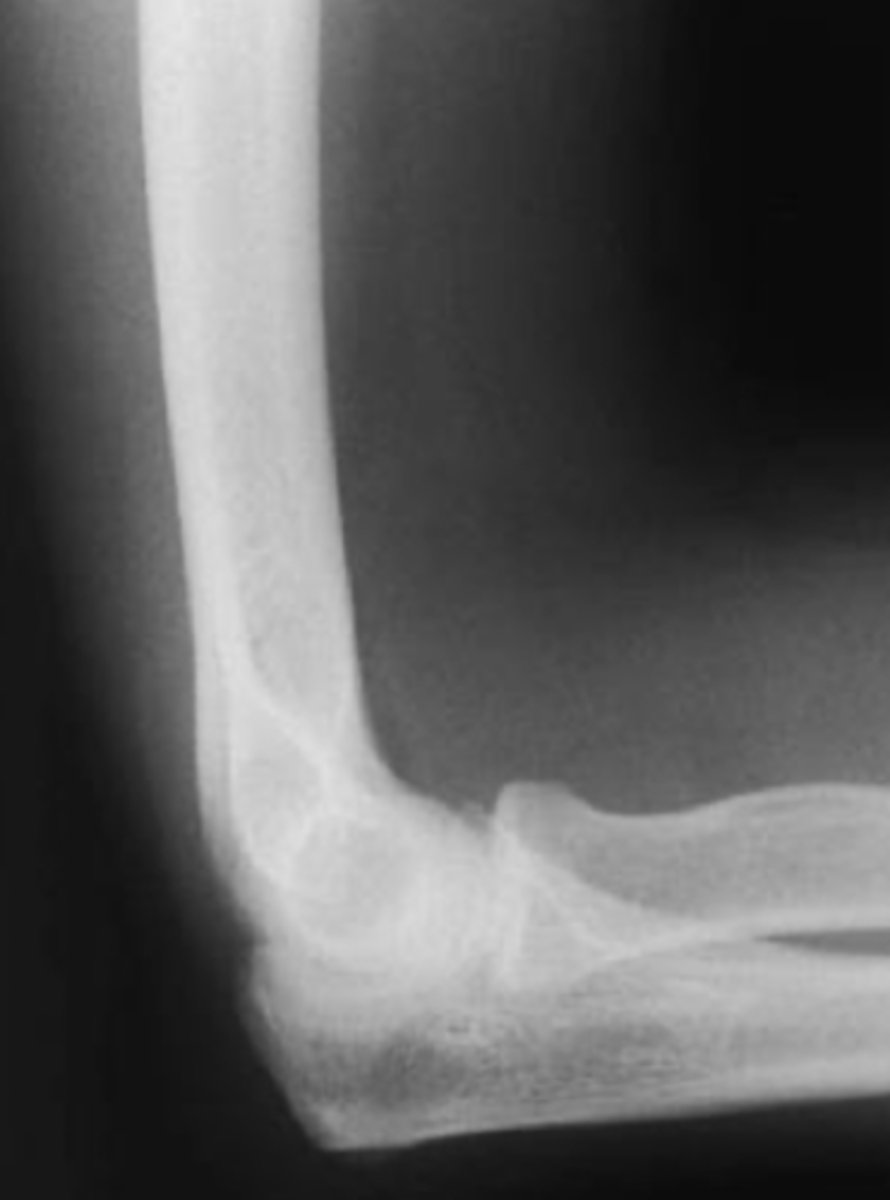

positive fat pad sign

What is the issue?